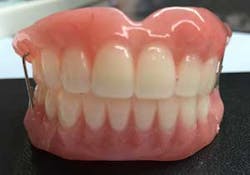

Six months postsurgery, a recommendation was made to the patient to remove the lower incisor teeth—Nos. 23, 24, 25, and 26—due to increased mobility and discomfort upon chewing. A lower anterior temporary partial was provided (figure 3).

Of course, proper records were obtained in order to fabricate the temporary provisional prosthesis (figure 7), upper and lower, to provide proper function, esthetics, and easy conversion.